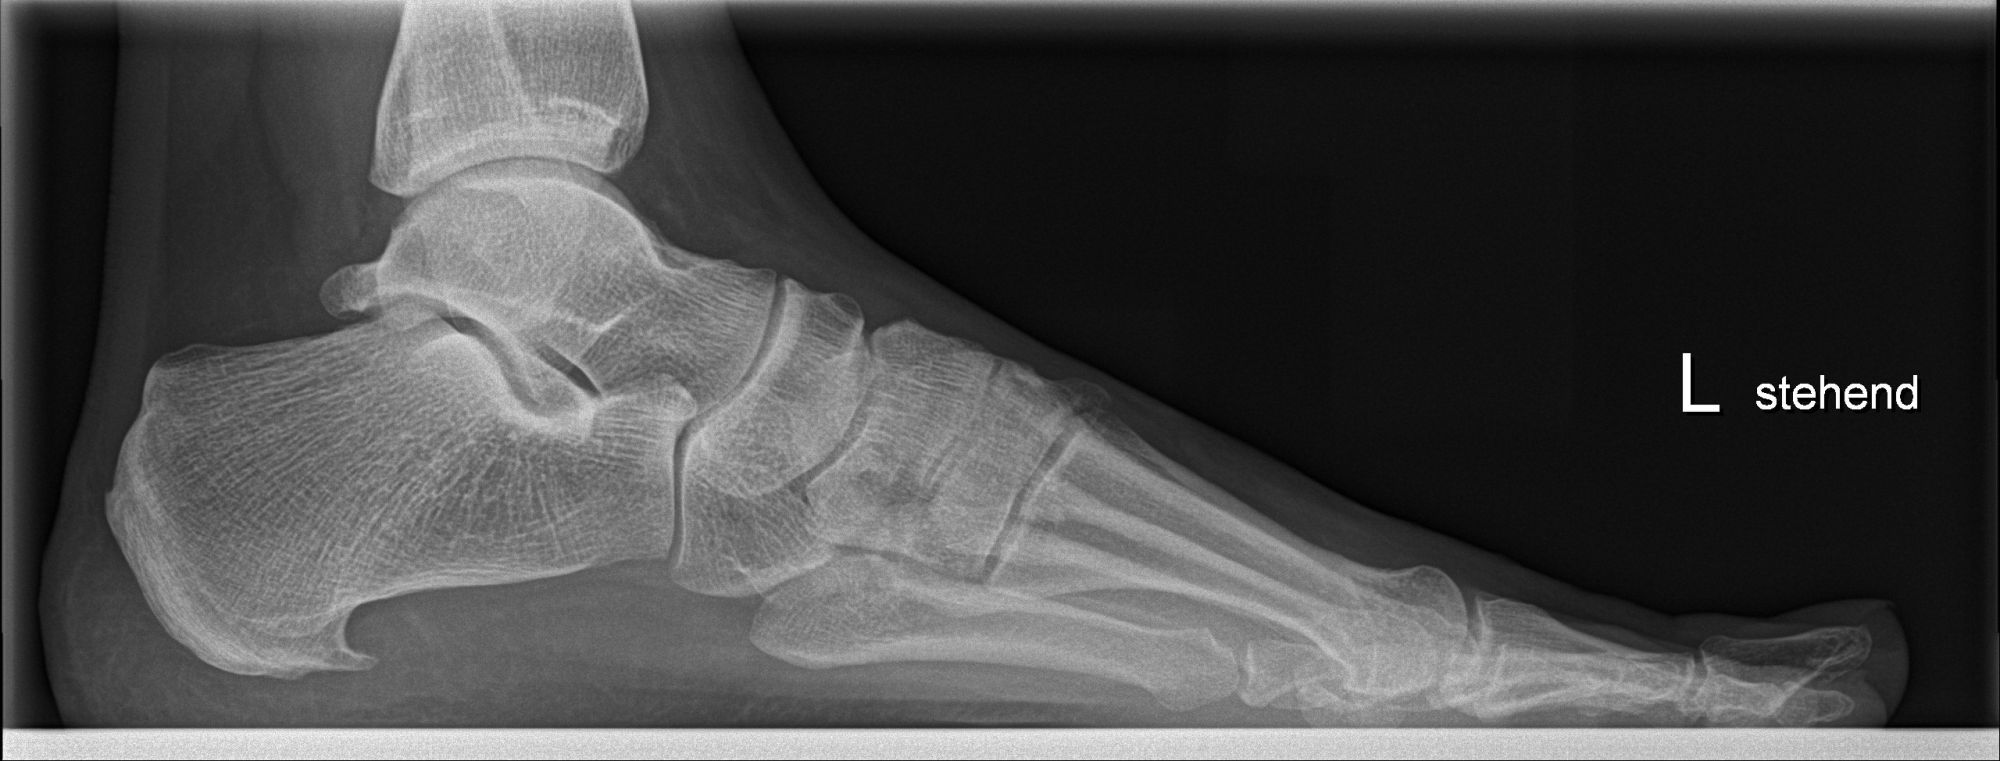

Abbildung 1: Plantarer und dorsaler Sporn im Röntgenbild und im MRT

Abb. 1a und Abb. 1b: großer dorsaler Fersensporn und ein minimaler plantarer Sporn, Patient, 50 Jahre.

Zum Lesen der Bildbeschreibung und zur Vollansicht bitte die Bilder anklicken. Bilder: Manfred Thomas.

Dorsaler Fersensporn: Dorsale Fersenschmerzen können auch durch einen echten dorsalen Fersensporn entstehen (siehe Abb. 1). Dieser entsteht als knöcherne Ausziehung durch Verkalkung der Achillessehne an ihrem Ansatz.